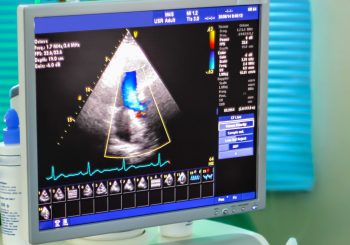

A new ultrasound technology that was recently tested could greatly improve the diagnosis of congenital heart disease in ...

A focused left ventricular transthoracic echocardiogram (TTE) option offered as a substitute for full ...